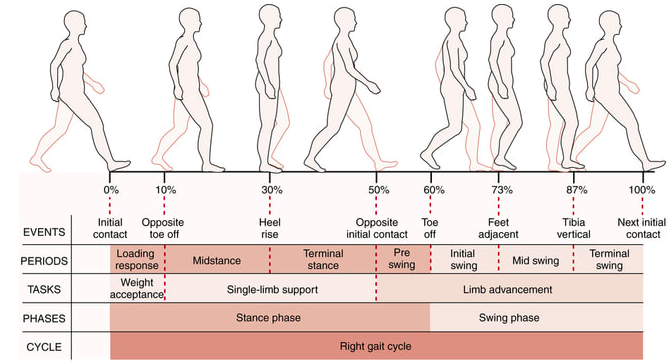

Il ripristino della perfetta efficienza del cammino rappresenta l’obbiettivo finale e il più importante di molti protocolli terapeutici.

Nonostante la sua apparente semplicità, sappiamo che esso è un intricato intreccio di interazioni tra cervello, colonna spinale, nervi periferici, muscoli, ossa e articolazioni.

Camminare richiede:

- attenzione cognitiva

- forza muscolare adeguata

- buon controllo motorio

Un movimento sbagliato, può dunque agire su diversi aspetti, ma si manifesta sempre come una asimmetria del gesto, comportando numerose compensazioni.